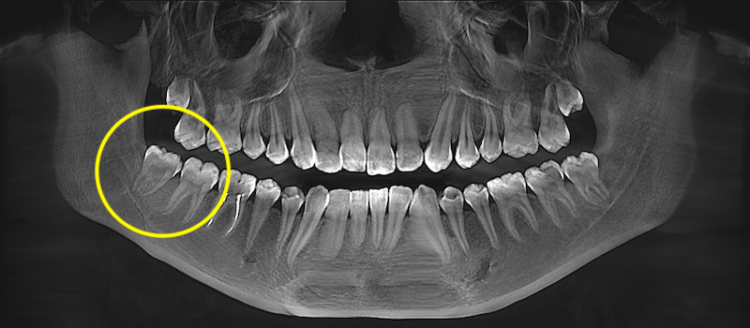

Просте й складне видалення зуба

Складність визначається не розміром зуба мудрості, а його положенням у кістці, напрямком росту, формою коренів та близькістю до анатомічних структур (нижньощелепний нерв, гайморові пазухи). Перед втручанням ці параметри оцінюються клінічно та на рентгені або КТ, що дозволяє спрогнозувати обсяг операції.

Зуб мудрості частково або повністю розташований у кістці (ретинований) або має неправильний напрямок росту (дистопований). Коронка може бути перекрита кісткою, а корені — близько до нерва або мати складну форму.

Ретинований зуб мудрості — це зуб, який повністю або частково не прорізався й залишається в кістці чи під яснами. Такий зуб може тривалий час не турбувати, але створювати ризик запалення, ураження сусіднього моляра або формування кісти.

Перед видаленням обов’язково оцінюється його положення на рентгені або КТ: глибина залягання, кут нахилу, форма коренів та контакт із нижньощелепним нервом. Це дозволяє спланувати доступ і мінімізувати ризики.

Дистопований зуб мудрості — це зуб, який прорізався або частково прорізався, але займає неправильне положення в зубному ряду. Найчастіше він нахилений у бік 7-го зуба, росте під кутом або зміщений у бік щоки чи язика.

Перед видаленням оцінюється його положення на рентгені або КТ: напрямок нахилу, форма коренів, контакт із сусіднім моляром і стан кісткової тканини. Це дозволяє зрозуміти, чи є ризик ураження 7-го зуба та обрати оптимальну техніку видалення.